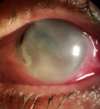

Como manifesta-se clinicamenta a incisão queimada?

Edema incisional + retração das margens e dificuldade de coaptação